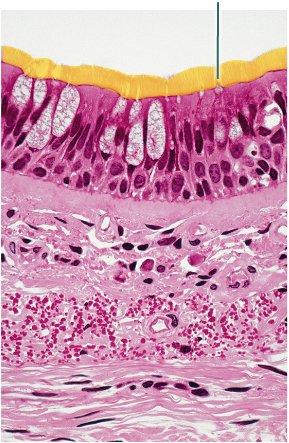

Which type of tissue is the highlighted region composed of?

stratum corneum

stratified squamous epithelium, keratinized

stratum spinosum

dermis

stratified squamous epithelium, keratinized

Which structure is highlighted?

stratified squamous epithelium, keratinized

stratified squamous epithelium, non-keratinized

stratified cuboidal epithelium

stratified columnar epithelium

stratified squamous epithelium, keratinized

Which layer of the skin is highlighted?

papillary layer of dermis

reticular layer of dermis

hypodermis

epidermis

papillary layer of dermis